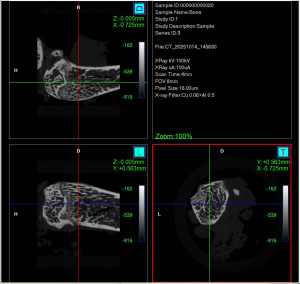

Developed SOP SOP(Standard Operating Procedure) Optical Images EM MR CT EPhys(EEG, MEG) Others Developed SOP SOP(Standard Operating Procedure) Optical Images EM MR CT EPhys(EEG, MEG) Others